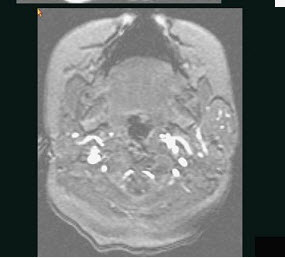

40岁,患者,左面部渐进性增大的包块,MRI检查如图所示,应考虑为()。

A、左面部毛细血管瘤

B、左面部囊肿

C、左面部脓肿

D、左面部脂肪瘤

E、左面部神经纤维瘤

A